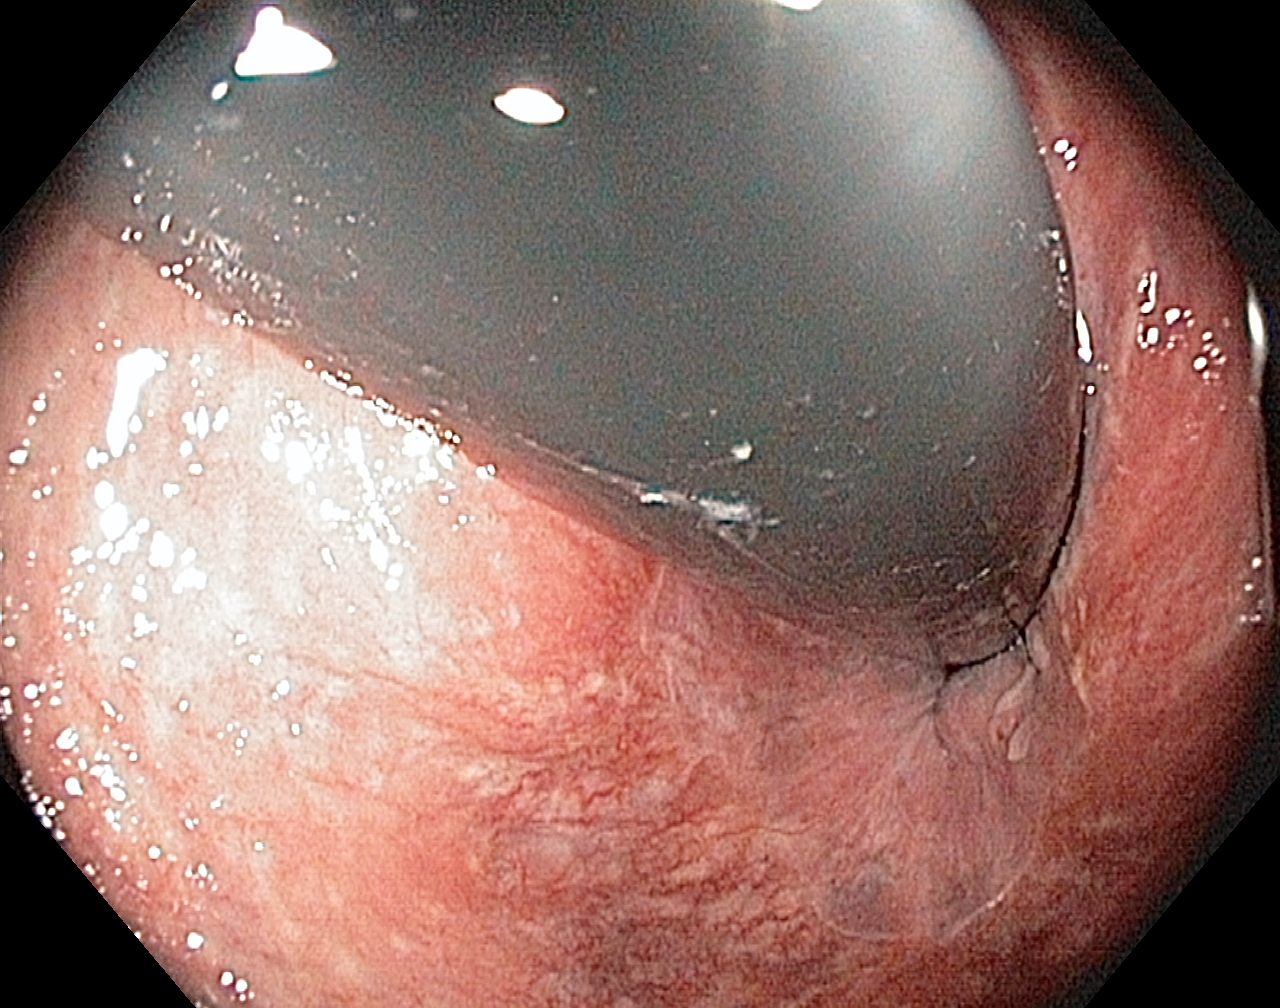

Linea dentata/anorectalis seen with the endoscope in an inverted position